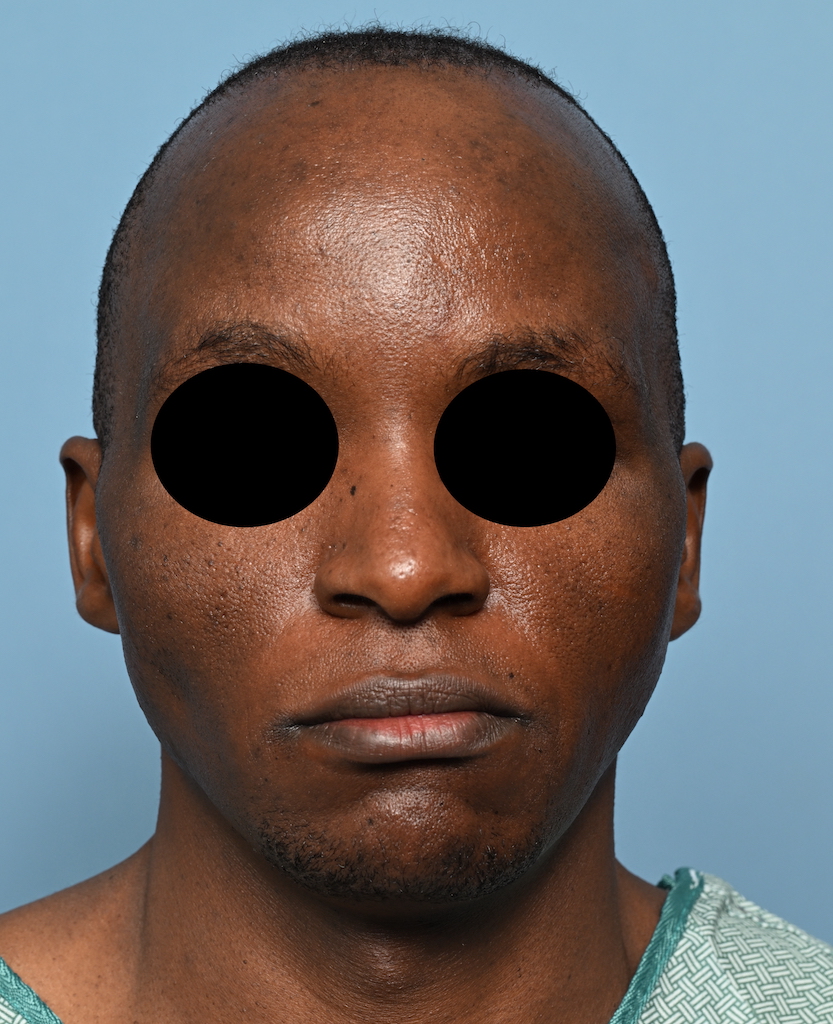

Patient 100

Desire for reshaping of an asymmetric flat back of the head in a shaved head male.

A combined back of the head reshaping procedure was done with a custom skull implant, sagittal ridge reduction and a right temporal muscle reduction.

Desire for reshaping of an asymmetric flat back of the head in a shaved head male.

A combined back of the head reshaping procedure was done with a custom skull implant, sagittal ridge reduction and a right temporal muscle reduction.